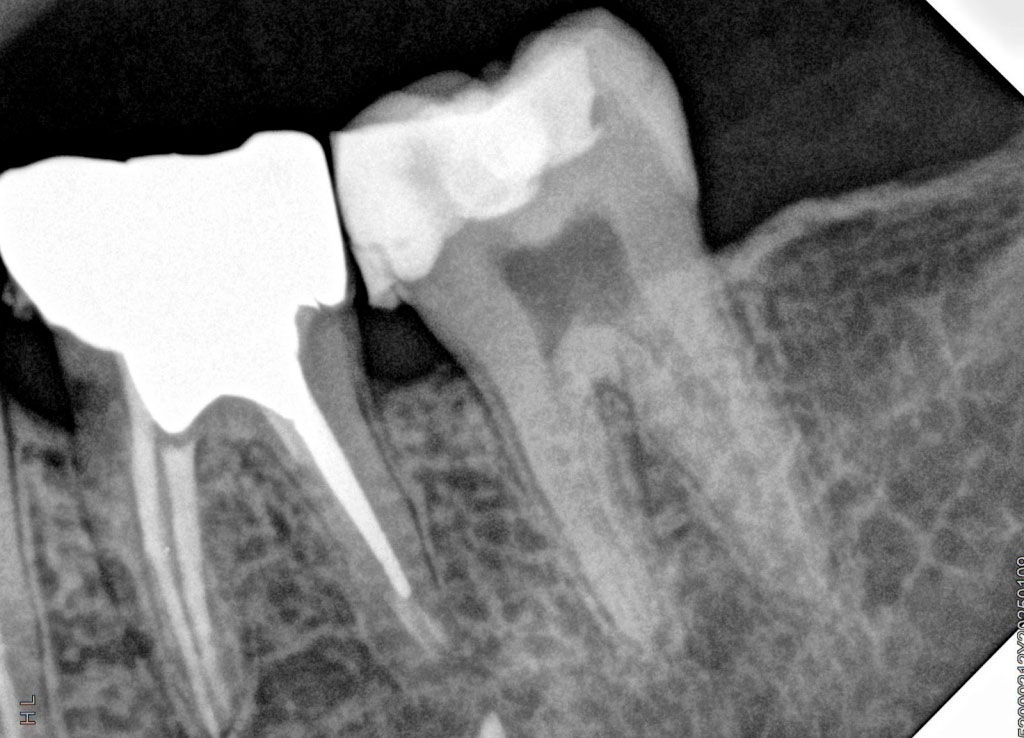

Сравнение качества снимков визиографов

Качество снимков зависит от множества критериев, приведенных выше. Давайте сравним снимки, полученные с визиографов различных производителей, по основным критериям: четкость, глубина, контрастность, детализация.

HDR-500 (HANDY)

unnamed (2).jpg

HDR-380 (HANDY)

unnamed (3).jpg

Если сравнивать снимки визиографов HANDY HDR 500 и HDR 380, то заметно, что аппарат последнего поколения — 380-й — значительно выигрывает по глубине снимков и детализации. Такое качество достигнуто благодаря технологии CMOS. Это комплементарный металл-оксид-полупроводник, используемый в детекторе. Он снижает уровень шума при считывании изображения, повышает чувствительность датчика и скорость передачи изображения. Кроме того, CMOS отличается более низким энергопотреблением, по сравнению с аналоговыми технологиями.

Тем не менее качество снимков HDR 500 для диагностических целей врачи признают достаточно высоким, и модель является одной из самых востребованных, благодаря самой низкой цене на рынке.

afkt9xm1su9xc2f8wqmq2fg16oudeixo-(1).jpg

Portview GIX-1 (Genoray)

unnamed (5).jpg

Если сравнивать в этой же ценовой категории визиографы HDR-380 HANDY и Portview GIX-1 от южнокорейского производителя Genoray, то мы видим практически идентичное качество снимков, при этом HDR-380 выгоднее по цене.

unnamed (6).jpg

unnamed (7).jpg

SOPIX 2 (Acteon Group)

unnamed (8).jpg

Мы видим идентичное качество снимков, которое зачастую несколько уступает по четкости, контрастности и глубине моделям последнего поколения азиатских производителей - в частности HANDY.

Таким образом, можно сделать вывод, что китайский производитель Handy Medical Equipment значительно потеснил рынок европейских и южнокорейских производителей визиографов, а аппарат последнего поколения HDR-380 по качеству снимков не уступает более дорогим конкурентным аналогам. При этом HDR-500 того же производителя, сохраняя самую низкую цену на рынке в этой категории, обеспечивает оптимальное качество снимков, приемлемое для большинства стоматологических клиник.